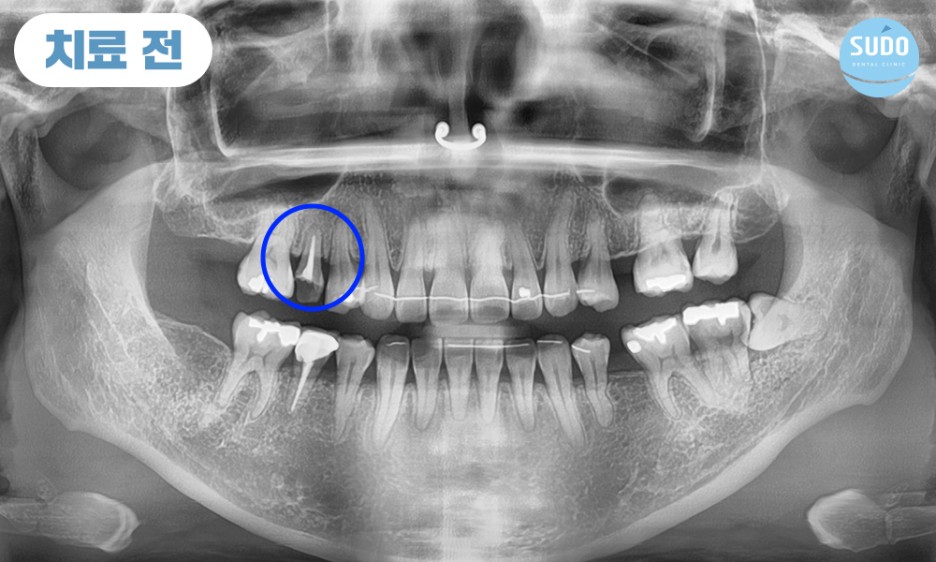

위 환자분은 30대 초반 여성분으로, 고등학생일 때 치료 받았던 금니가 빠져 저희 수도치과에 내원해 주셨습니다.

그 부분만을 확대하여 x-ray 사진 촬영해 본 결과 치아 뿌리 안쪽까지 심한 충치로 인해 발치 후 임플란트를 진행하셔야 하는 상태였습니다. 임플란트 경험이 없으셨던 환자분을 위해 수도치과 의료진들의 충분한 치료 설명을 통해 발치 후 부산영도임플란트 식립 계획을 수립하였습니다.